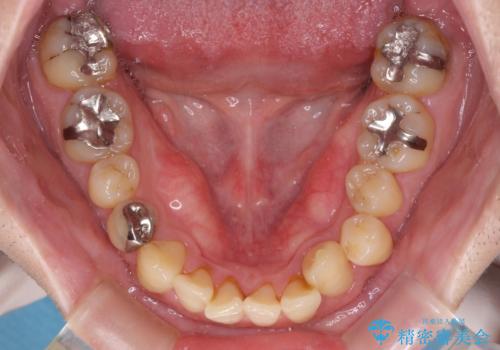

- デコボコした前歯をセラミックできれいに揃えたいとのことで来院された患者様です。

歯を削って整えることは簡単ですが、健全な歯を削って後悔してからでは遅いため、矯正治療を提案しました。

はじめは矯正治療の期間が長いことに悩んでいらっしゃいましたが、ある程度整えば満足するだろうとのことで、インビザラインにて矯正治療を行うこととしました。

左上の犬歯が欠損しているため、正中の位置や奥歯の咬み合わせが理想的にならない点を了承していただきました。

インビザライン矯正は、1日22時間を目安に装着する必要がありますが、しっかりと装着してくださったので、順調に治療を進めることができました。